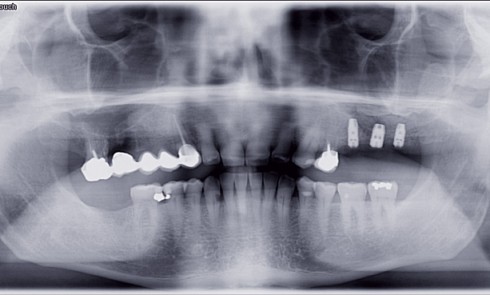

Quelques semaines après la parution de cet article, nous recevions un message de l’unde nos confrères exposantune situation problématique consécutive...Consommation de boissons non alcoolisées et érosion dentaire